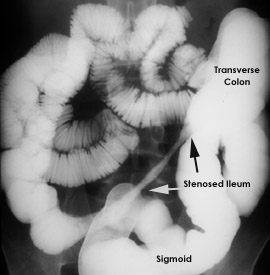

Figure 4. Recurrent Crohn's Disease of the Distal Ileum After Colon Resection.

The right colon and terminal ileum were resected with the margins free of disease; but, a year later, the patient developed loose stools and was found to have a narrowed segment of distal ileum proximal to the ileal-transverse colon anastamosis (progressing left to right in the figure). Note the absence of adjacent loops in the area of the featureless, narrowed ileum caused by its wall thickening. The more proximal loops of small bowel (left and upper abdomen), though somewhat dilated, appear to be normal. Because recurrence such as this is common in Crohn's disease, resection is reserved for patients with complications such as obstruction or fistulae between the diseased bowel and other organs.